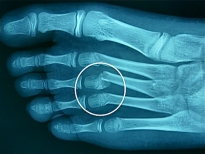

Exemple d'atteinte du cartilage de croissance du 1e orteil (pied gauche):